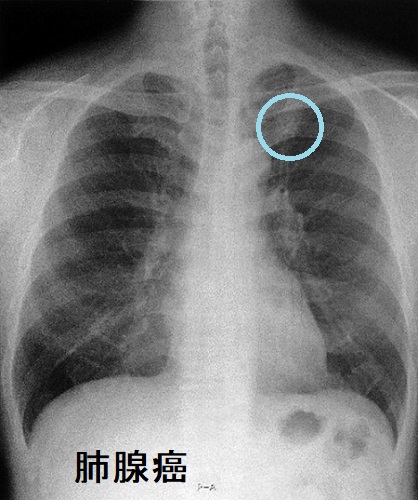

肺腺癌

原発性肺腺癌は末梢肺に発生する場合が多く、粘膜下病変主体であるため喀痰細胞診で診断できる可能性は低い。気管支鏡検査で病理組織を採取すれば確定診断できる。

肺腺癌 胸部X-p写真